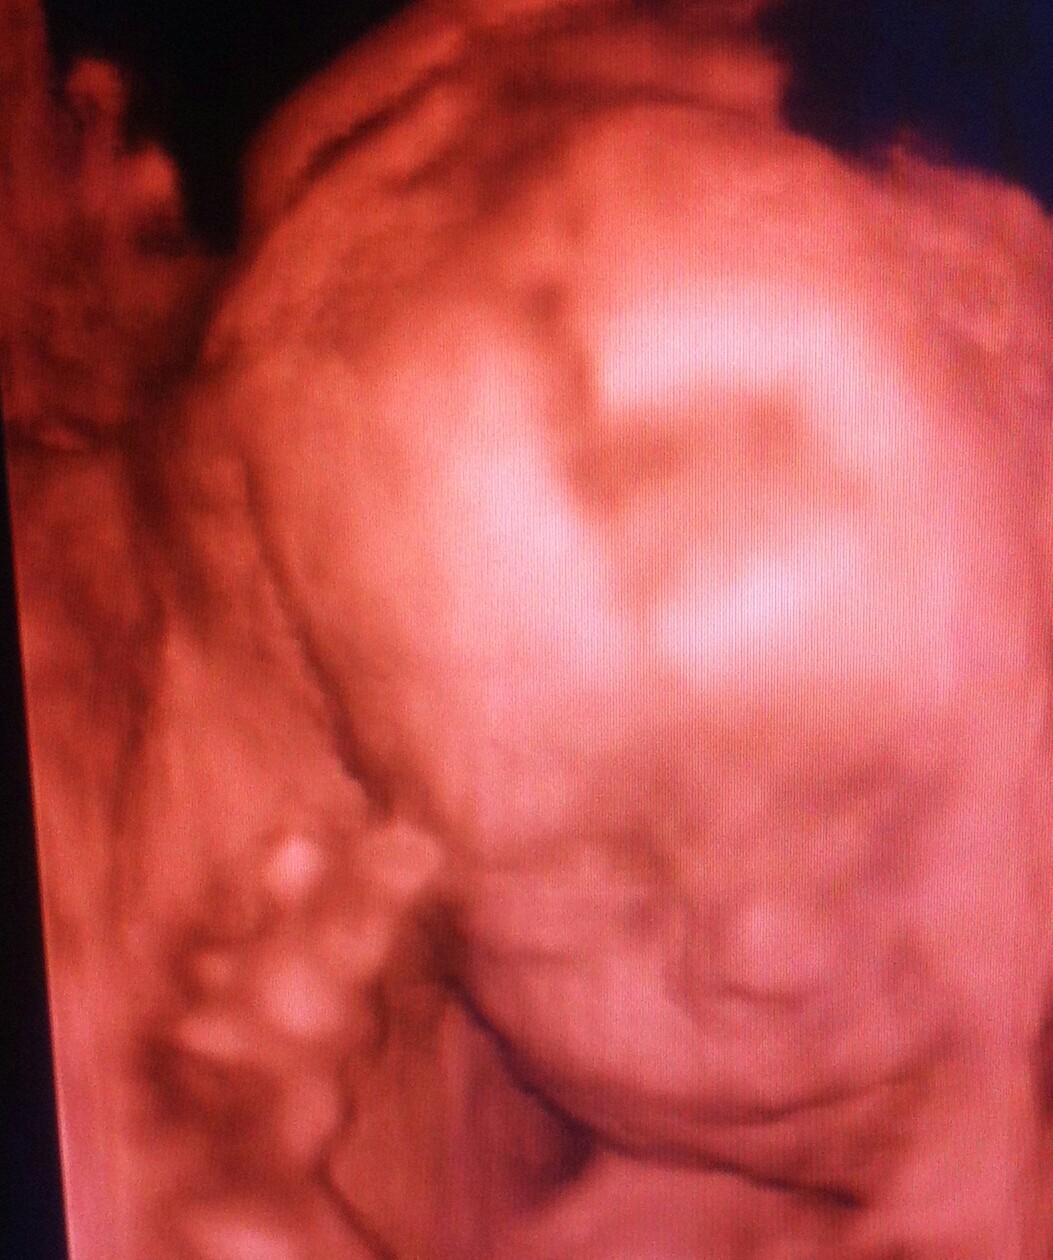

Fanka BB :)

Gratuluję udanych wizyt.

Mój mały poprzecznie. Na razie się jeszcze nie stresuję, choć starszy jak się obrócił głową w dół koło 20 tygodnia, tak już został.